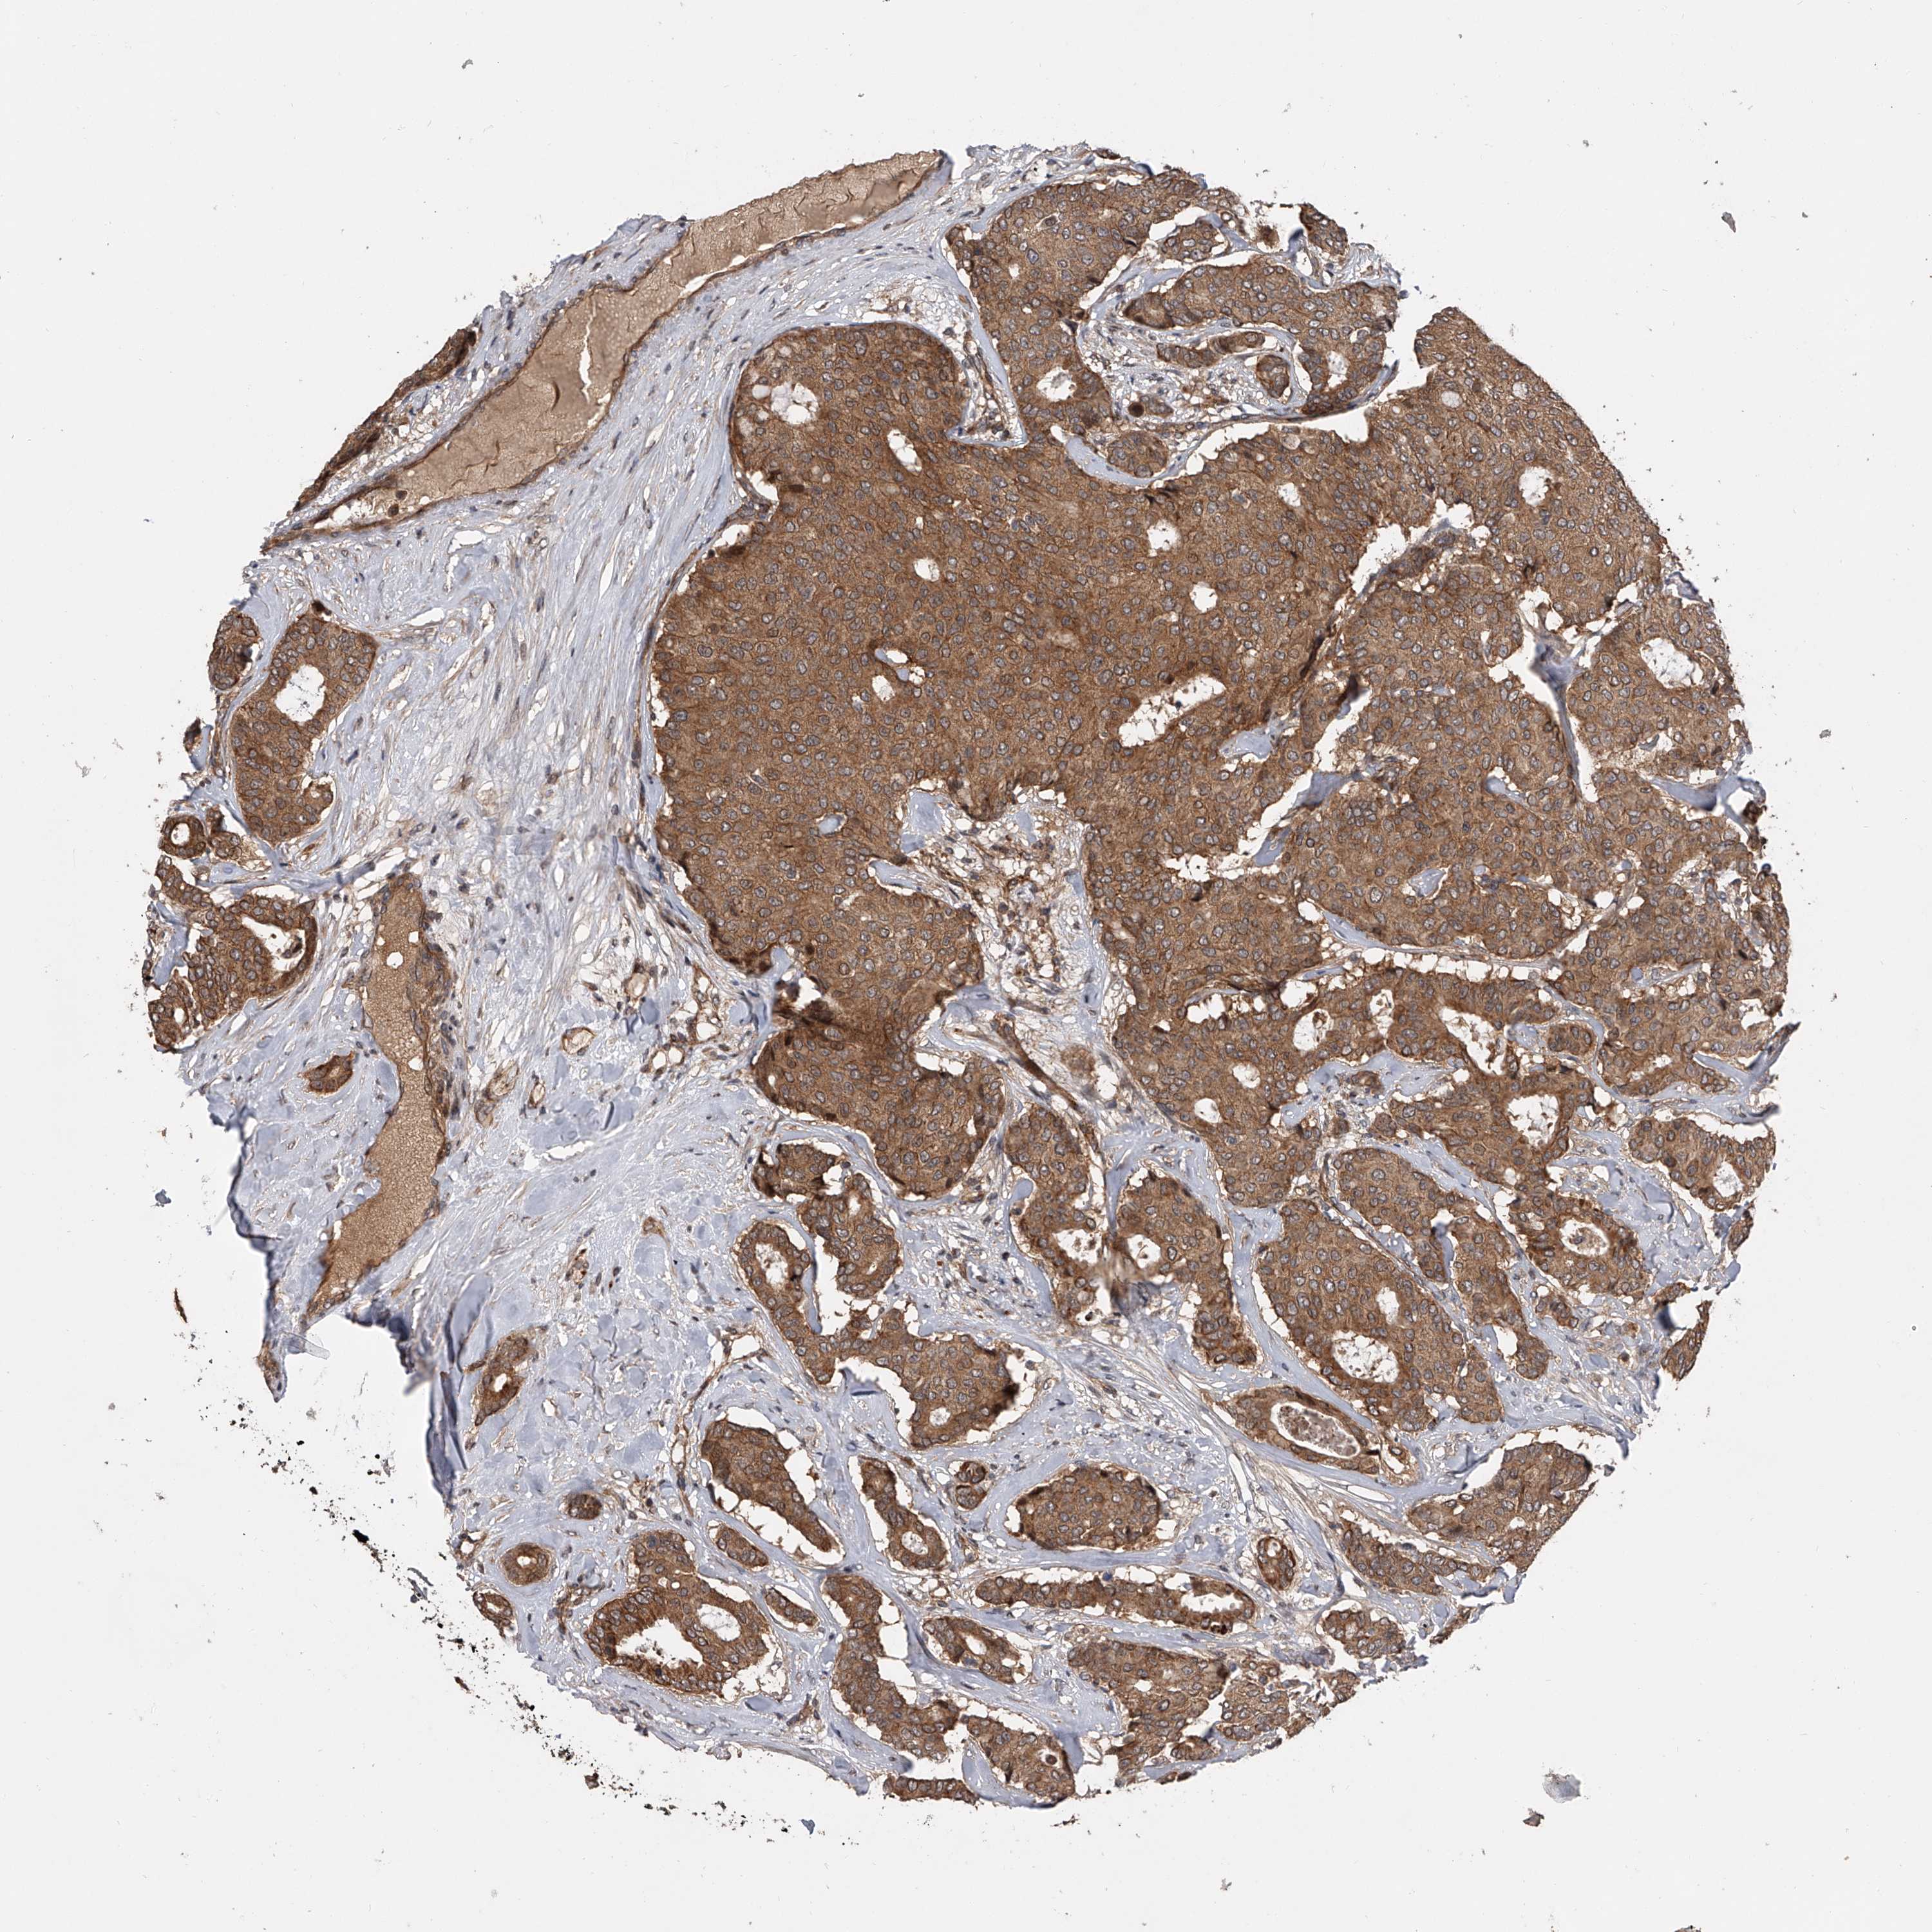

CANCER BREAST CANCER Show tissue menu

BRCA TCGA BRCA VALIDATION PROTEIN EXPRESSION

Breast cancer

Human cancer

USP47 is not prognostic in Breast Invasive Carcinoma (TCGA)